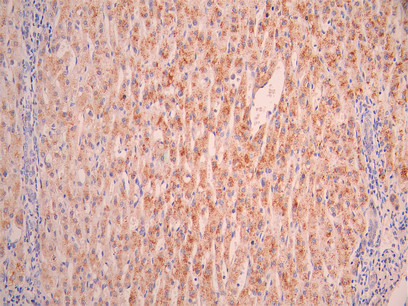

• IHC image of CSB-RA019483MA1HU diluted at 1:50 and staining in paraffin-embedded human liver tissue performed on a Leica BondTM system. After dewaxing and hydration, antigen retrieval was mediated by high pressure in a citrate buffer (pH 6.0). Section was blocked with 10% normal goat serum 30min at RT. Then primary antibody (1% BSA) was incubated at 4°C overnight. The primary is detected by a Anti-Human lgG, Fcy Fragment Specific labeled by HRP and visualized using 0.05% DAB.